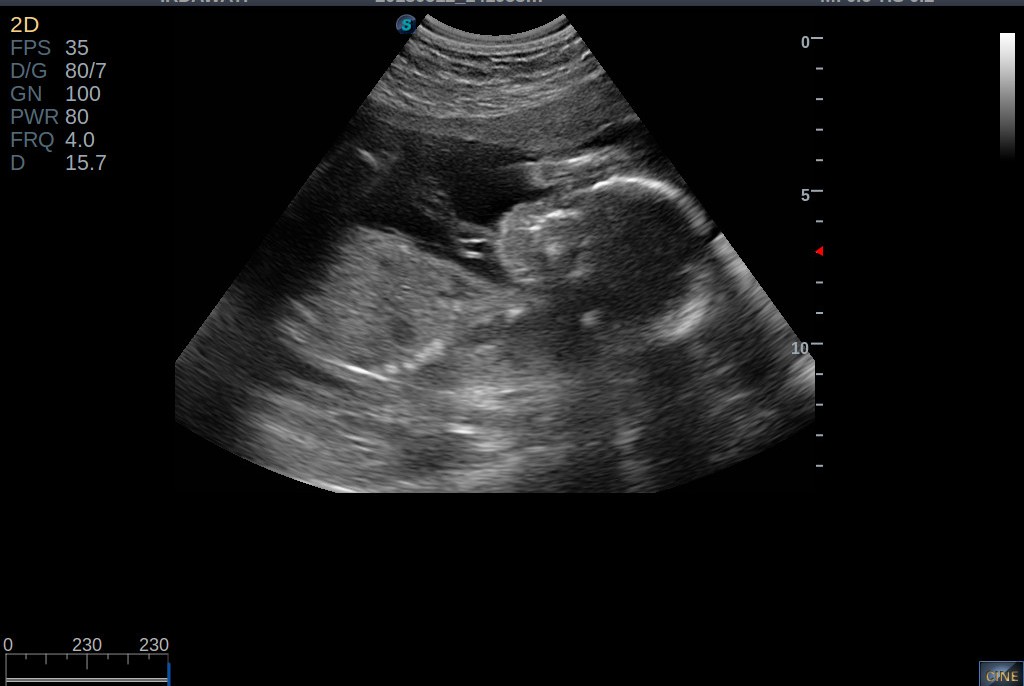

Nak Share Kat Sini Baru Blik Dr Klinik Scan Baby Dh Masuk 37week Dh Huhu Dah Dekat Sgt Dh Nk Bersalin Selama Tempoh Masa Mengandung Nie Aku Duk Bayangka